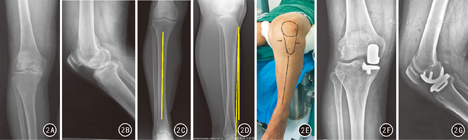

术后拍摄膝关节正侧位X线片,均在透视导向下完成,以保证放射线束平行于假体表面。在正位片上,测量出胫骨假体内外翻角(E角),0°为中立位,内翻为负角度,外翻为正角度(图1A)。在侧位片上,测量出相对于胫骨轴线的胫骨假体后倾角度(F角),7°为中立位,伸直为负角度,屈曲为正角度(图1B)。影像评估者为经过培训的放射科医师,为减小测量误差,采用测量3次,并取平均值为测量数据。根据Oxford单髁手术操作手册中的术后X线评分,将E、F角超过中立位±5°定义为力线不良。

两组术后所有患者无切口感染、脂肪栓塞或下肢深静脉血栓形成。术后第3天复查膝关节正侧位X线片,测量观察组E角绝对值1.25°±0.52°、F角绝对值1.08°±0.51°,对照组E角绝对值4.02°±0.53°、F角绝对值3.88°±0.54°,差异均有统计学意义(t=13.451、13.592,P值均<0.01)。两组均无力线不良。典型病例见图2。